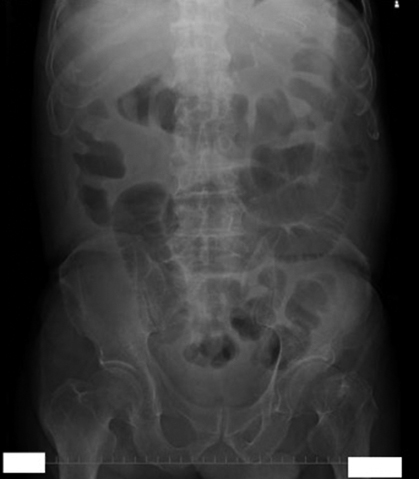

現病歴②:抗生剤変更後,蠕動は弱いものの,排便が認められた.第50病日に便中CD toxin陽性となり,腹部膨満が増悪し,腹部単純レントゲンで小腸ガス貯留の増悪を認め(Fig. 5)イレウスを伴う劇症型Clostridium difficile感染症(以下,CDIと略記)と診断した.経口投与ではVCMが結腸に到達しないと判断し,横行結腸癌術後吻合部への負荷を回避し,罹患した全結腸および直腸への確実なVCM直接投与を目的に同日緊急手術を施行した.

Abdominal X-ray picture demonstrated the dilated ileum and implied deterioration of the ileus.